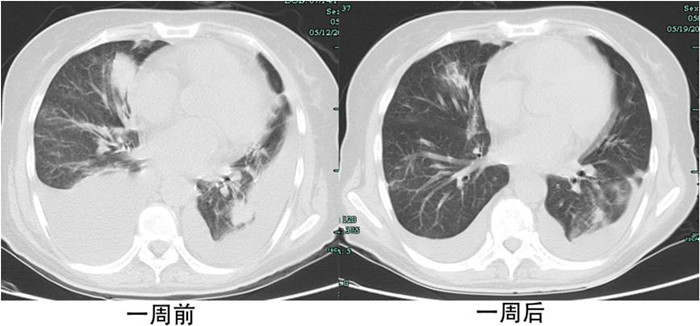

用藥一天后,劉女士咳嗽及胸悶癥狀得到了緩解,一周后,咳嗽及胸悶完全消失,兩周后雙肺的轉移病灶及癌性淋巴管炎也明顯減輕,甚至雙側胸腔積液也明顯減少。